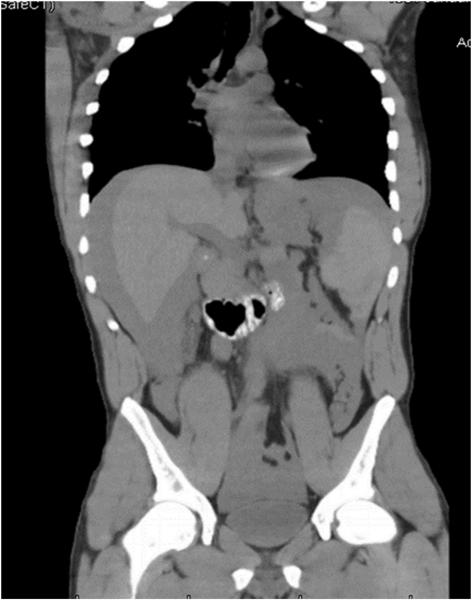

一名23岁男性患者因腹痛于我院急诊就诊,既往有酗酒史,入院前一天患者鼻内吸入可卡因,随即发生多次腹痛和呕吐。查体发现患者意识状态清醒,GCS评分15分,心率120次/分,血压105/55mmHg,腹膜炎迹象明显。行腹部CT检查提示腹腔内出血,脾破裂,如图1,图2。患者血红蛋白11mg/dL,尿液测试检测可卡因阳性,而患者并无任何外伤史。

图1、2 全腹CT提示:腹盆腔内大量出血,脾破裂